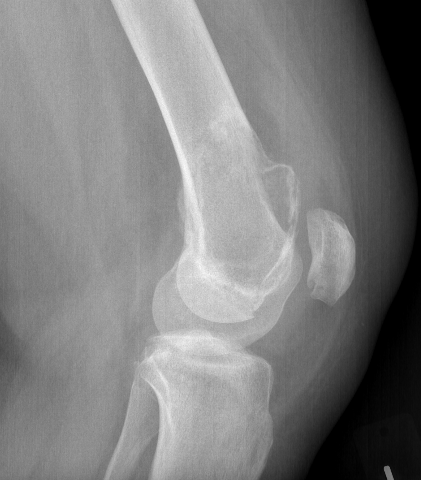

X-ray

Eccentric, sharply demarcated lytic lesion

- no sclerosis around lesion

- narrow zone of transition

- metaphysis, extending into epiphysis

- no mineralization